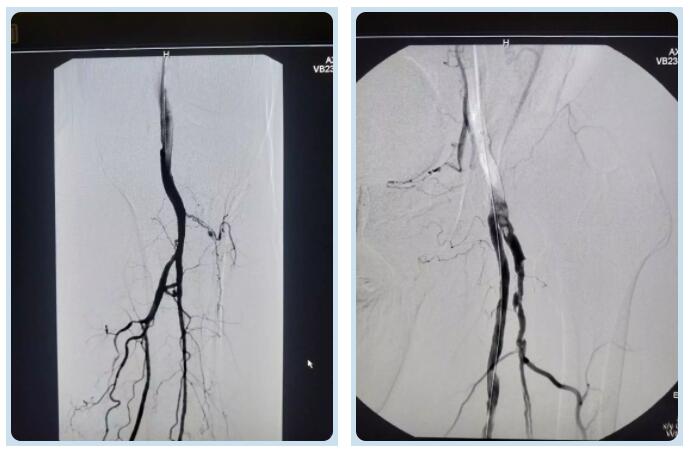

股總動(dòng)脈及腘動(dòng)脈堵塞處

股總動(dòng)脈及腘動(dòng)脈取栓后

劉主任抵達(dá)醫(yī)院后,快速為王大爺制定了周密的介入方案,經(jīng)過完善的術(shù)前準(zhǔn)備,劉主任帶領(lǐng)團(tuán)隊(duì)為王大爺進(jìn)行介入手術(shù)。經(jīng)動(dòng)脈造影,發(fā)現(xiàn)王大爺下肢大血管有兩處動(dòng)脈血栓,分別在大腿根部及膝關(guān)節(jié)部位,情況十分危急。劉綿春主任決定立即為患者實(shí)施股總動(dòng)脈及腘動(dòng)脈取栓術(shù)。介入科醫(yī)師們利用動(dòng)脈穿刺技術(shù)及導(dǎo)管技術(shù),將直徑2.6mm的導(dǎo)管插入血栓位置進(jìn)行吸取。30分鐘、60分鐘、90分鐘……時(shí)間在一分一秒中度過?!按笸雀咳∷ǔ晒Γ中g(shù)完成一半!”劉主任的聲音里帶著一絲絲喜悅,同時(shí)叮囑身旁的同事不能有一絲懈怠,顧不及早已被汗水浸濕的手術(shù)衣,也顧不及疲憊不堪的身體,劉綿春主任和他的團(tuán)隊(duì)繼續(xù)進(jìn)行著介入手術(shù)。凌晨一點(diǎn)十五分,再次造影顯示右腿恢復(fù)血流,經(jīng)過醫(yī)護(hù)人員的共同努力、密切配合下,歷時(shí)三個(gè)半小時(shí),這場(chǎng)微創(chuàng)手術(shù)終于以成功告終。王大爺冰涼、紫紺的腿恢復(fù)了溫暖和紅潤(rùn),效果可謂立竿見影,而且沒有留下傷痕,讓患者及家屬感到十分欣喜。術(shù)后,患者被送往骨外科病房,經(jīng)過醫(yī)護(hù)人員精心護(hù)理和治療患者已下床活動(dòng)。